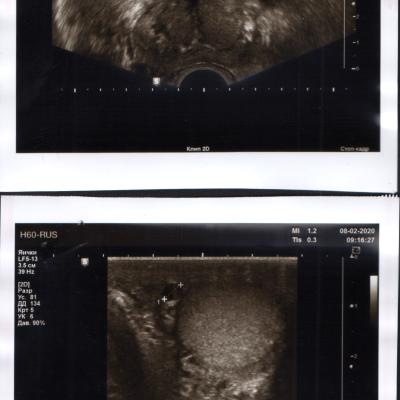

В 1989 г. в НИИ урологии мне удаляли камень в лев.почке. Почти тогда же обнаружили простатит и года два-три назад установили аденому предст.железы. Принимал аводарт, Омник, Даводарт. Мучает частая беготня "по-малому" ночью и вялая потенция. Хотелось бы совета. Спасибо